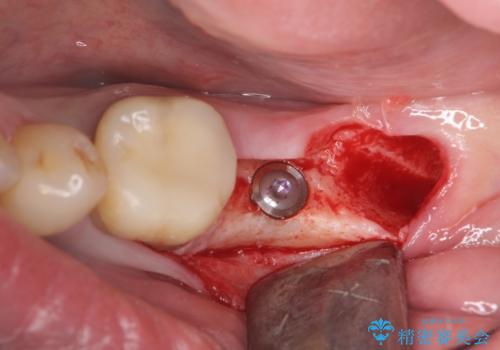

最後方臼歯のインプラント補綴

- 40万円(ストローマンインプラント・カスタムチタンアバットメント・メタルボンドクラウン)費用は治療当時の料金となります

今回はしっかりと噛むことができ、取り外しの必要のないインプラントによる補綴を行いました。

インプラント治療の注意事項(リスク・副作用など)

- 外科手術のため、術後に痛みや腫れ、違和感を伴います